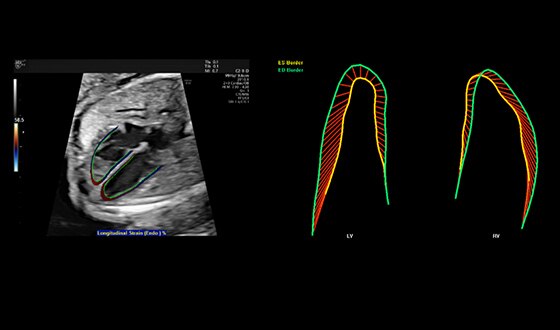

Fetal heart contractility demonstrated with fetalHQ